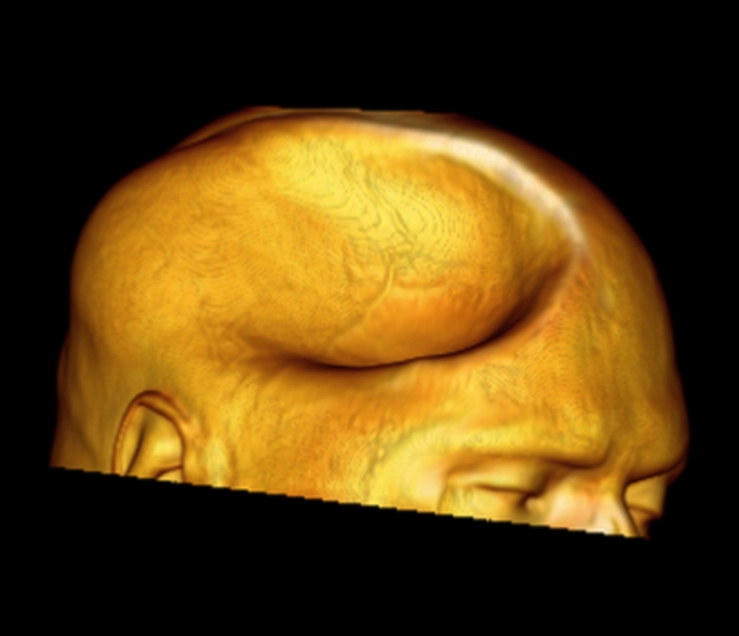

Tụ máu dưới cân Galea (Subgaleal hematoma)

16/03/2026